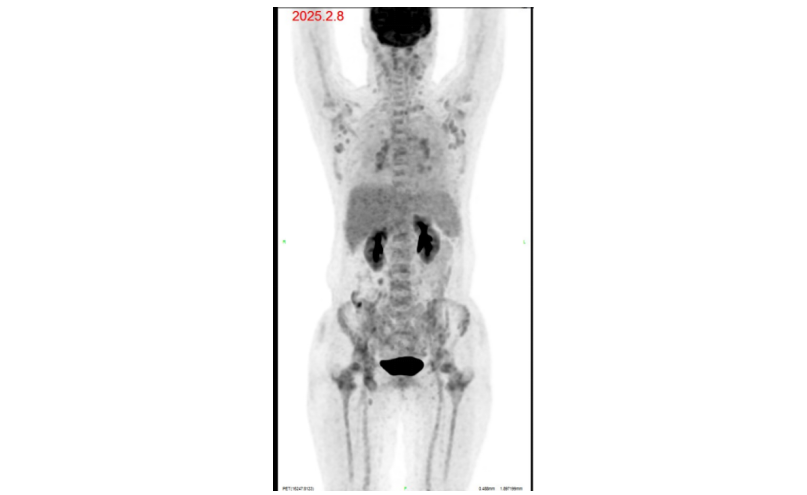

,刺激造血后好转,化疗同时送检基因突变位点,提示BTK C481S突变。治疗3周期后患者血钙再次升高,完善PET-CT提示全身多发高代谢淋巴结,较前部分新增,考虑疾病进展,再次行新增高代谢淋巴结活检,病理提示仍为CLL/SLL加速期。

图5. 2025-02-08 PET-CT表现